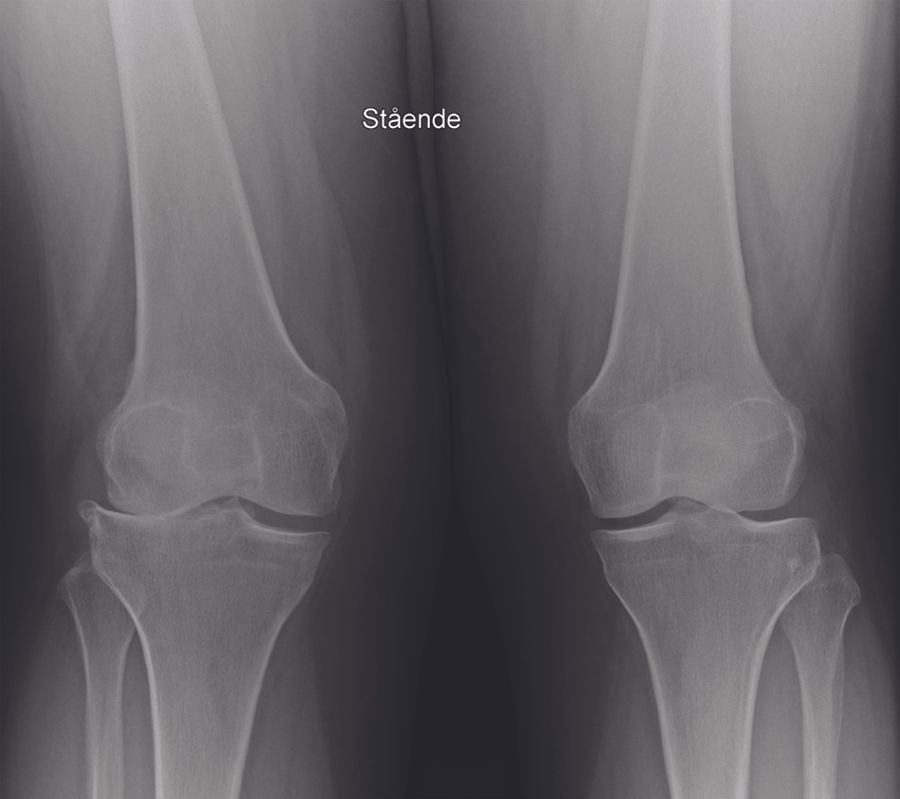

Radiographic assessment (fig. 1A-C)

My routine radiographic examinations of patients referred with pain believed to origin from knee OA include weight-bearing AP, lateral, and skyline views. These may be supplemented by valgus and varus stress radiographs, a Rosenberg view and / or MRI of the knee as needed. It is fundamental to establish bone-on-bone OA in the lateral compartment. Due to the specific features of lateral compartment OA bone-on-bone may not present on the weight-bearing radiograph with the knee extended. If there is any doubt about the bone-on-bone diagnosis in the lateral compartment supplemental imaging should be applied. On the weight-bearing AP view it is also assessed if there is preserved cartilage in the medial compartment. If in doubt a varus-stress radiograph may be helpful to assess this, and at the same time a varus stress will show correction of valgus deformity, opening of the lateral compartment, and indirectly that the LCL is functionally intact. In the lateral radiographic view the relative position of the femur and tibia should be assessed. If the femur is very posteriorly positioned it may be a sign that the ACL is degenerative and torn. The skyline view is specifically assessed for the presence of severe bone-on –bone OA. In general I only find MRI examination necessary in younger patients, particularly if the knee hos posttraumatic OA, in which case MRI can give good information about cartilage damage and degeneration in the lateral and the remaining compartments, as well as the status of cruciate ligaments.